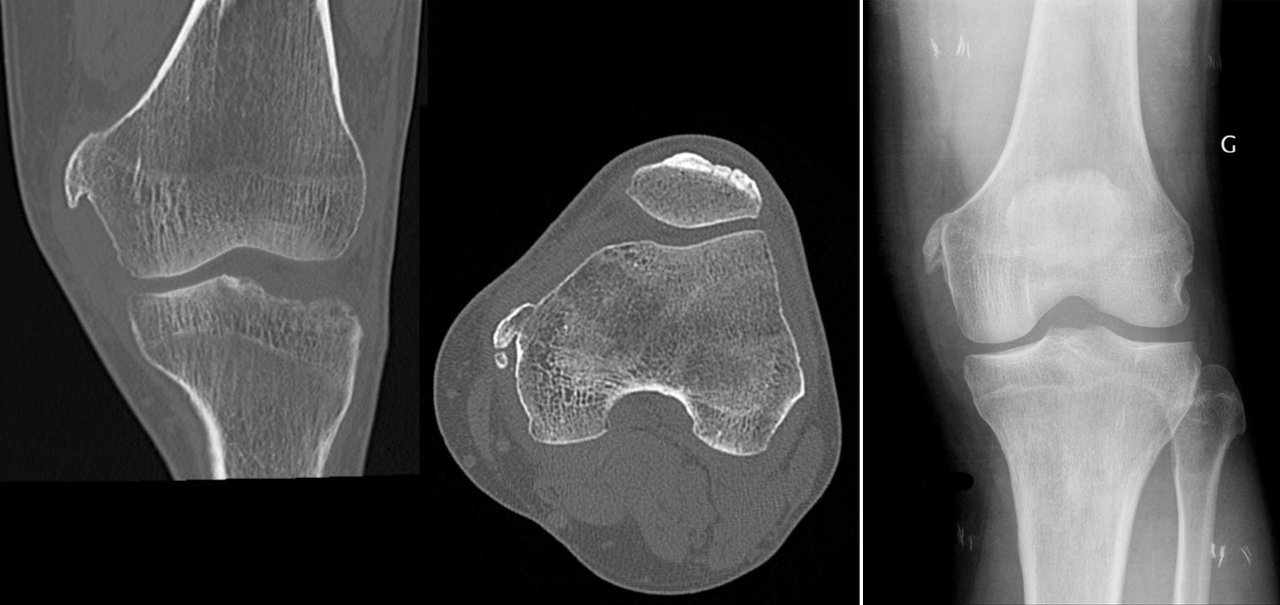

Une radiographie standard du genou gauche, complétée par une tomodensitométrie, est réalisée.

L’ossification de Pellegrini-Stieda correspond à une ossification post-traumatique du ligament collatéral médial, survenant classiquement après des entorses répétées du genou. Le diagnostic est essentiellement radiologique : l’imagerie montre une ossification linéaire, bien limitée, juxtacorticale, située au niveau de l’insertion proximale du ligament collatéral médial, sans signe d’agressivité osseuse. C’est une pathologie bénigne et le traitement est le plus souvent conservateur. À retenir : toute ossification médiale du genou chez un patient avec entorses répétées doit faire évoquer ce diagnostic.